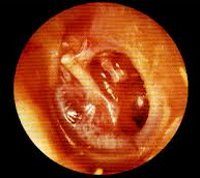

Наиболее важным моментом в диагностике адгезивного среднего отита является выявление характерной отоскопической картины заболевания. Отоскопия (простая и с увеличением) определяет втяжение барабанной перепонки, ее помутнение и наличие рубцовых изменений, в некоторых случаях вызывающих деформацию перепонки. В полости слуховой трубы также визуализируются тяжи и спайки, иногда полностью облитерирующие ее просвет.

Диагноз устанавливают по совокупности характерных для адгезивного отита проявлений — типичный анамнез, отоскопическая картина (мутная барабанная перепонка, отсутствие или смещение светового конуса, втяжение барабанной перепонки, сухая перфорация, известковые отложения в толще натянутой части барабанной перепонки). Исследование слуха: акуметрия — определение уровня восприятия шёпотной или разговорной речи, тесты с камертонами — проба Ринне отрицательна, проба Вебера — латерализация, проба Желе положительная. При тональной аудиометрии отмечают повышение порогов восприятия звуков через воздух, интервал разной степени между кривой костной и воздушной проводимости. Речевая аудиометрия позволяет исследовать восприимчивость слов на разных частотах, что определяет социальную степень слуха у больного. У маленьких детей прибегают к игровой аудиометрии. Тимпанограмма уплощена без выраженного пика (тип В). Для дифференциальной диагностики между адгезивным средним отитом, отосклерозом и нейросенсорной тугоухостью прибегают к регистрации акустического рефлекса, слуховых вызванных потенциалов, регистрации отоакустической эмиссии.